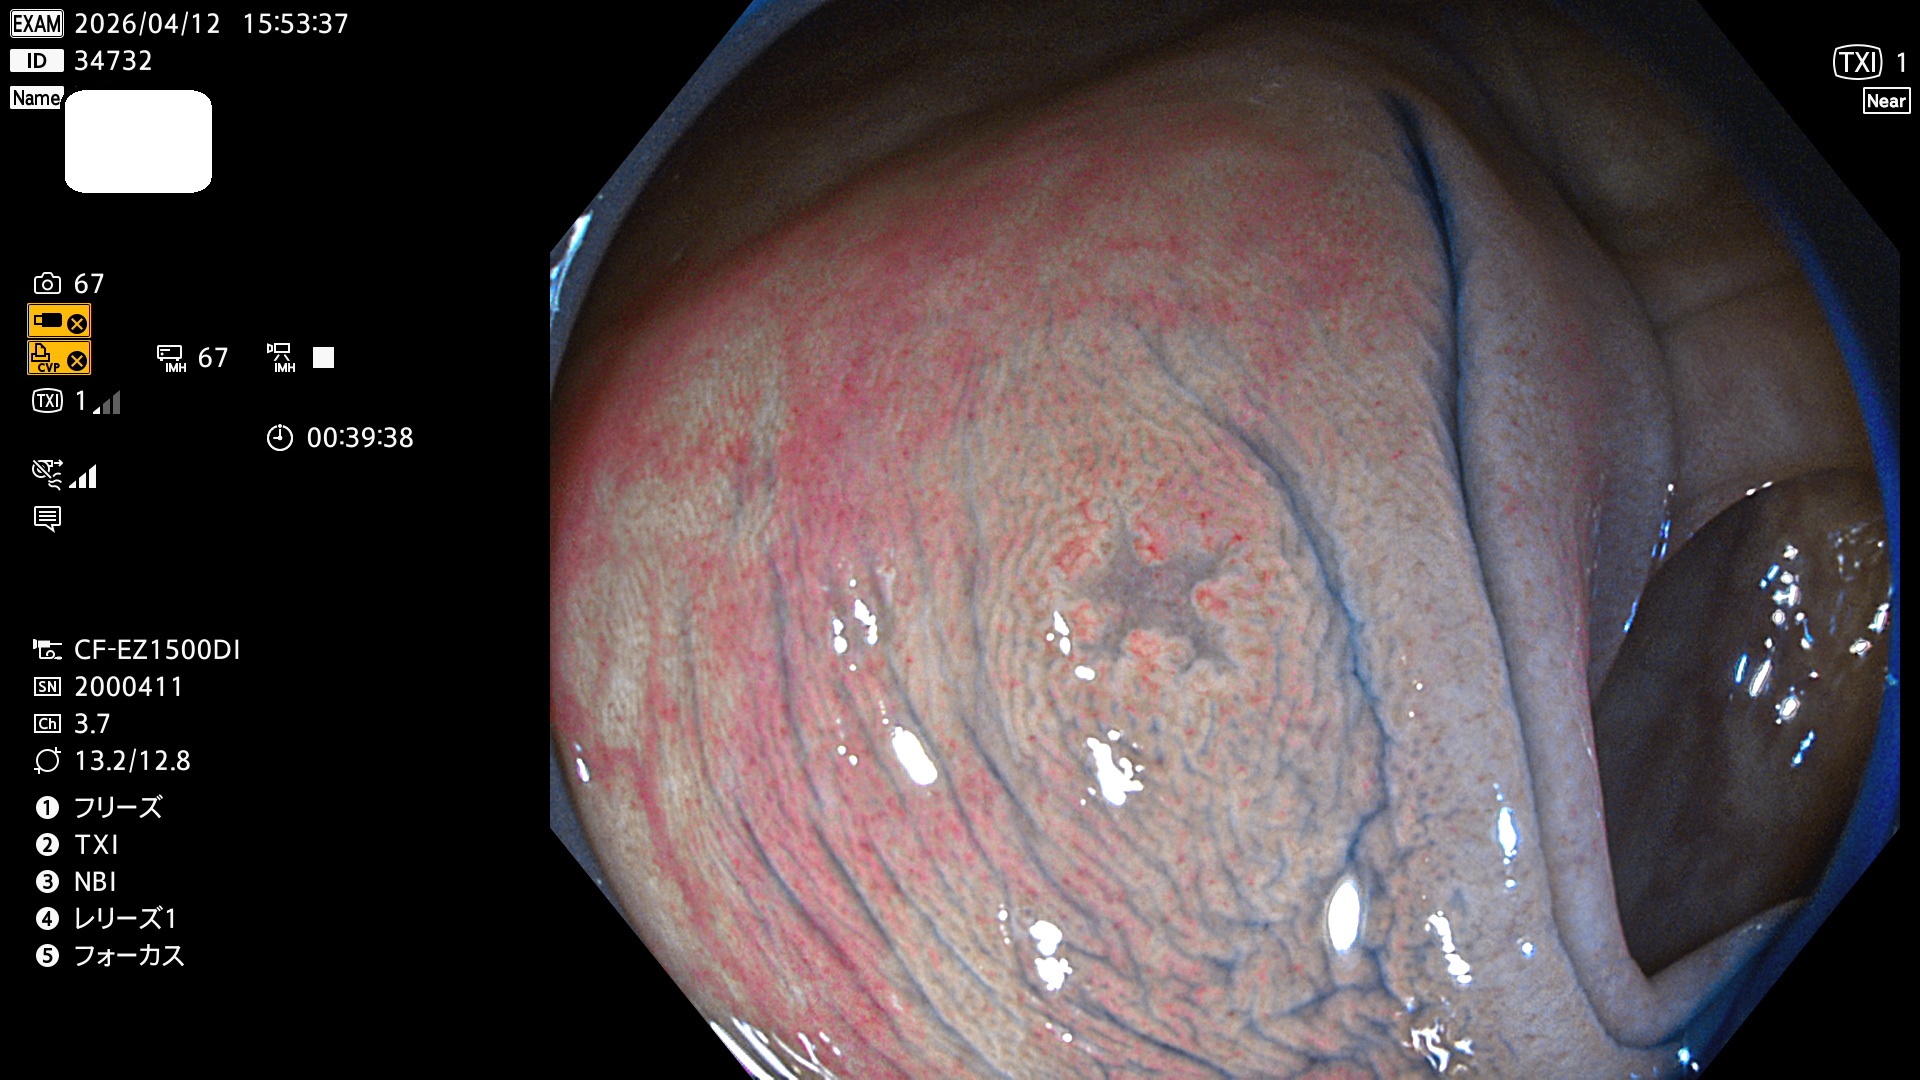

完全に平坦な物をUb、陥凹している物をUcと呼びます。Ubは認識が困難で、Ucはびらん(炎症)と紛らわしいために見落とされやすく、「内視鏡後・大腸癌」の原因になります。

専門的)Uc=De Novo癌? 内視鏡の解像度が低かった時代、このような説もありました。しかし今日の高精度内視鏡では良性の微小なUc型腺腫(APC遺伝子異常の腺腫)が日常的に見つかります。Ucこそが多段階発癌(Adenoma-Carcinoma Sequence)のMain Routeです。

毎週の検査(木・金・土・日)に発見されたUbとUc型・腺腫を、その週の日曜の夜にUPし1週間、提示します。

2026年4月9日〜4月12日の4日間(40件)で6個 (Uc_ADR=6個/40人=15%)